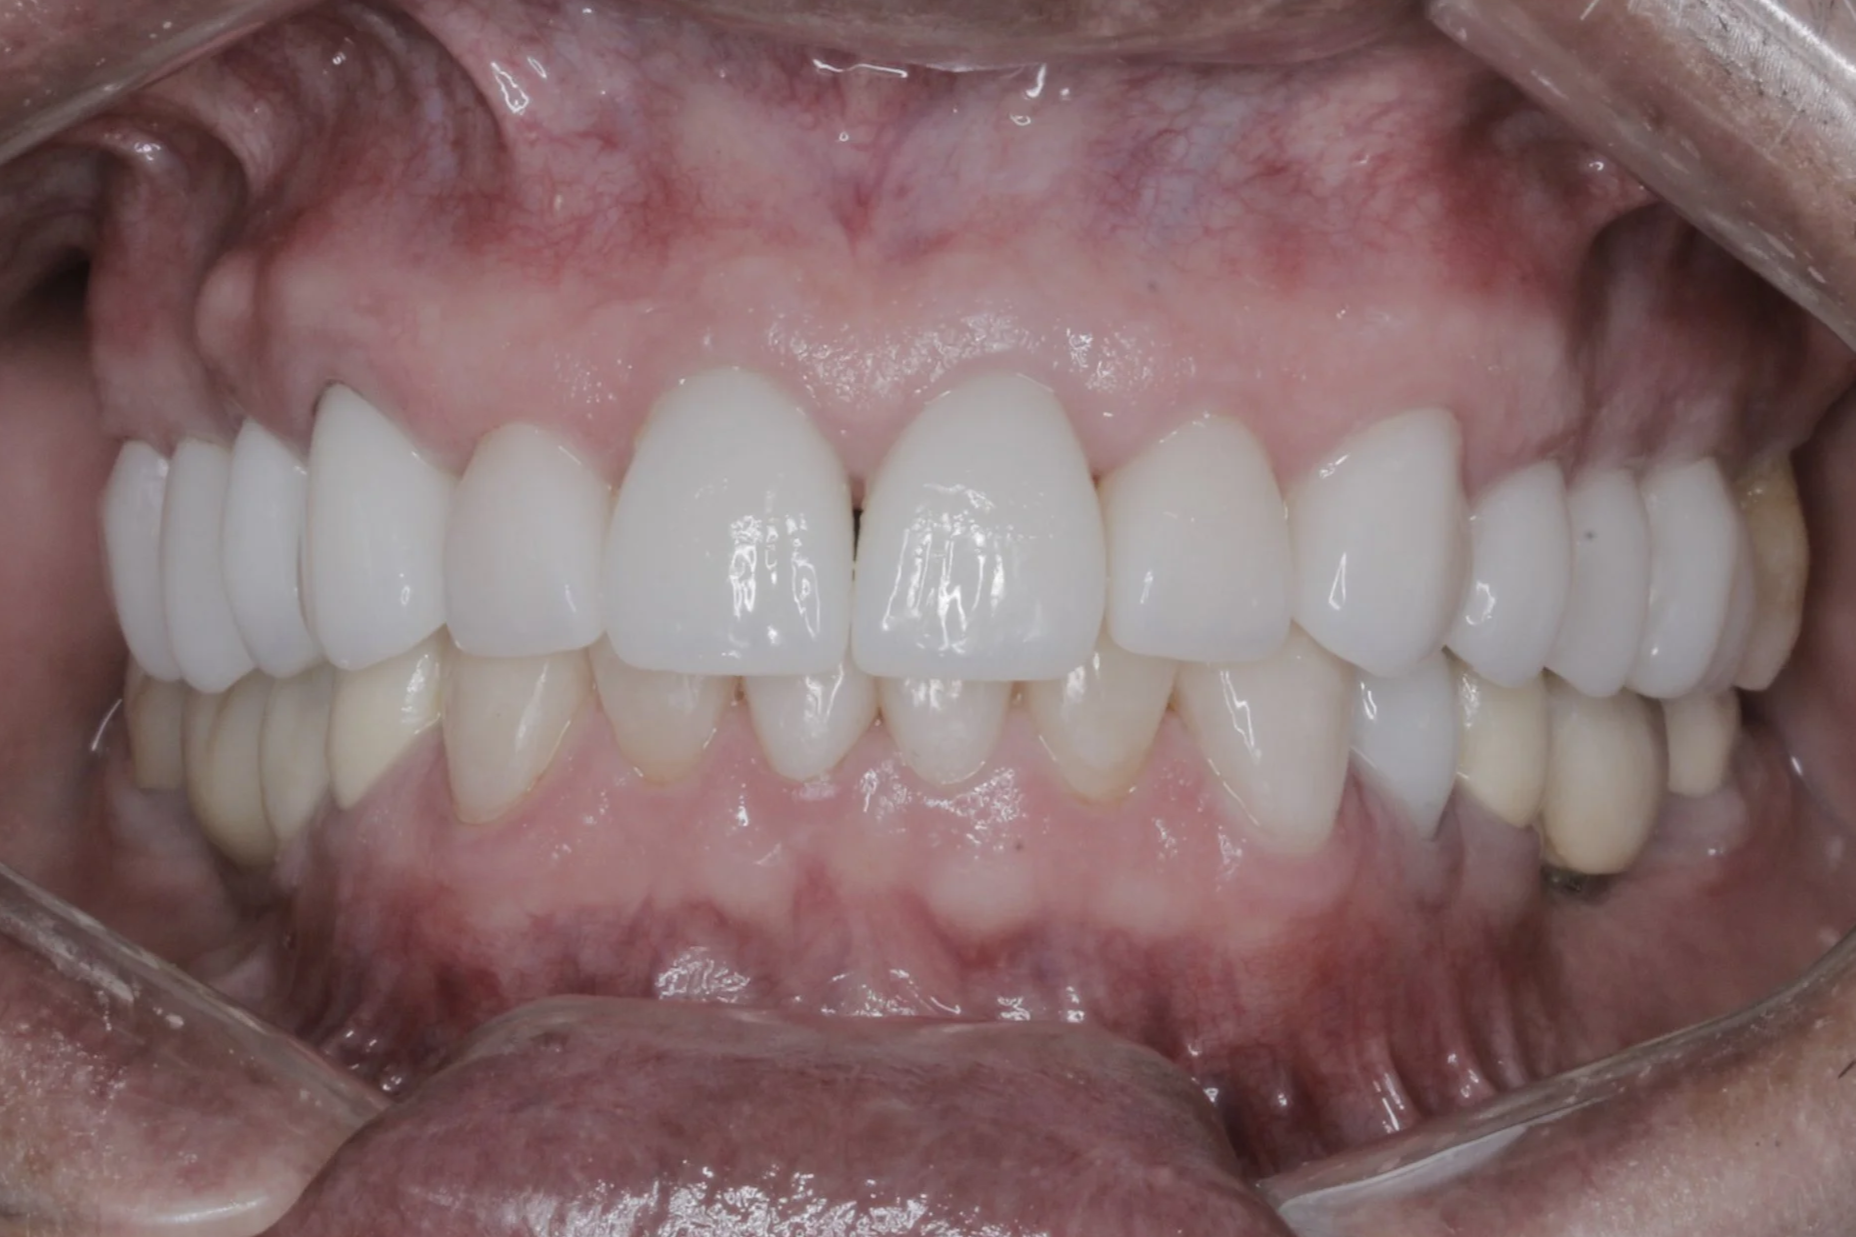

Después

Reemplazo de puente fijo + coronas

Nuevas coronas y carillas libres de metal de todos los dientes superiores.

Resultado final